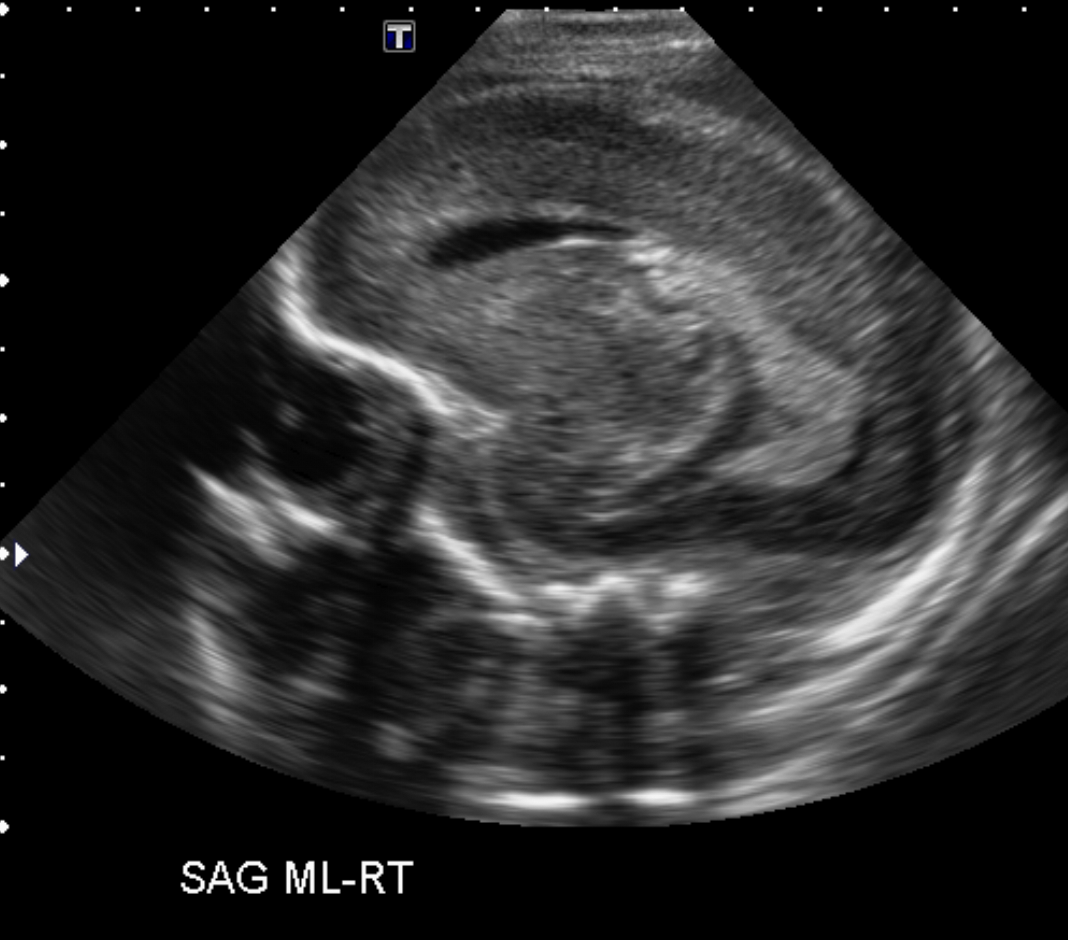

Info Images Findings Impression Reco/Acuity Case Images View Images / Launch Visage Case Notes History Full term infant. We are asked to evaluate posterior fossa cyst. Exam Gray scale and Doppler Ultrasonographic examination of the head. Prior Study N/A Dicom View Reference Material

Section 1 Submit Findings Case149 Findings Brain The brain is immature. Yes No There is under-sulcation and open sylvian fissures. Yes No There is/are multiple hypoechoic areas in the periventricular white matter. Yes No There is/are multiple hyperechoic areas in the periventricular white matter. Yes No There is diffuse cerebral edema with diffusely increased echogenicity of the brain parenchyma and loss of grey white matter differentiation. Yes No The thalami/basal ganglia are hypoechoic. Yes No There is periventricular calcification. Yes No There is intra-parenchymal calcification. Yes No CSF spaces/ventricular system There is a prominence of the extra axial fluid spaces. Yes No There are debris/septations in the extra axial fluid spaces. Yes No There are debris/septations in the ventricles. Yes No There is a subdural collection on the right/left side. Yes No There is prominence of the ventricular system. Yes No There is an asymmetry of the ventricular system. Yes No There is a cavum septum pellucidum. Yes No There is a midline shift towards right/left. Yes No The choroid plexus is bulky/lobulated. Yes No There is a choroid plexus cyst measuring… Yes No There are debris/clots in the occipital horn. Yes No There is a posterior fossa cyst measuring… Yes No The tentorium is elevated/depressed. Yes No The lateral ventricle/s are dilated. Yes No The third ventricle is dilated. Yes No The 4th ventricle is dilated. Yes No There are pseudo cysts. Yes No Germinal matrix hemorrhage (Only in the premature infants): Please do not answer if the patient is a full term. There is a germinal matrix hemorrhage, consistent with a grade I hemorrhage. Yes No There is an intraventricular extension consistent with a grade II hemorrhage. Yes No There is an intraventricular extension with the dilatation of ventricles, consistent with a grade III hemorrhage. Yes No There is an intra-parenchymal extension, consistent with grade IV hemorrhage. Yes No On color Doppler examination, the Resistive index in the anterior cerebral artery is… There is a loss of the diastolic flow on the Doppler exam. Yes No There is altered vascularity on Doppler imaging. Yes No There is an AVM in the region of… Yes No